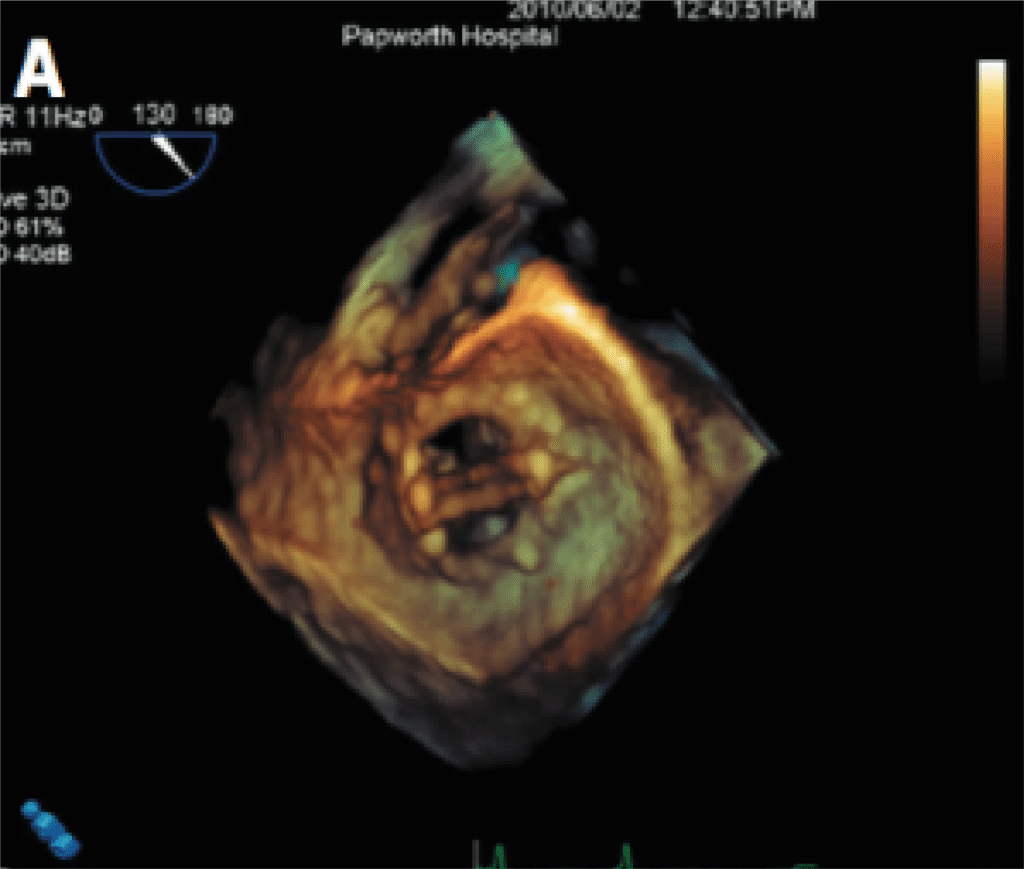

3D Echo

3D Echocardiography enhances traditional imaging by offering dynamic, three-dimensional views of the heart, providing superior anatomical detail especially useful in valve assessments and surgical planning.